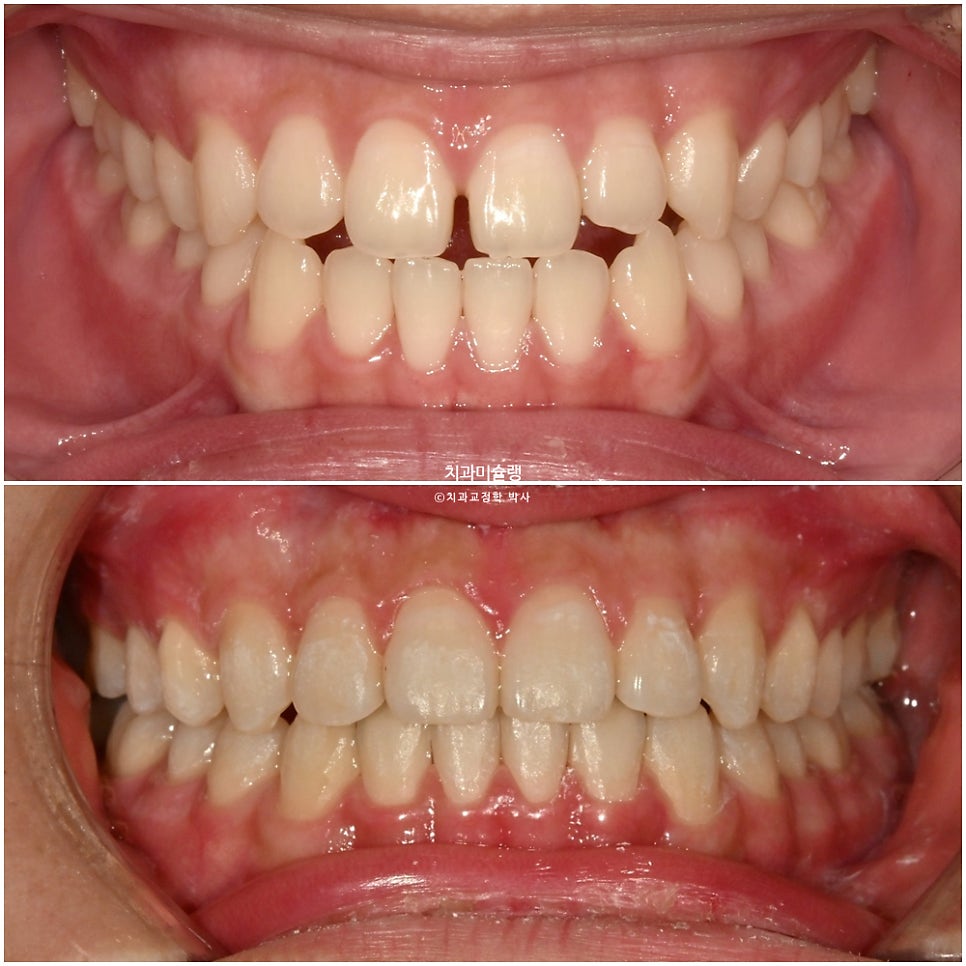

치료 전후 비교 결과

이제 전후 비교 보겠습니다.

간단한 교정이 아니고서야 미진한 부분 전혀 없이, 즉 재제작 없이 치료를 마무리하기 힘든데 해외에서 가끔 내원하면서도 장치를 열심히 껴준 덕에

쉽지 않는 난이도의 치료를 재제작 없이 마무리 했습니다.

교합관계는 3급에서 1급으로 개선되었죠.

안모 변화

이제 안모 비교 보겠습니다.

깔끔해진 미소

적절한 앞니 교합

아랫입술이 소량 뒤로 들어가며 입매가 미미하게나마 개선되었습니다.

아래 턱은 변화 없으며 아래 앞니가 뒤로 들어갔습니다.

양악수술 없이 턱은 들어갈 수 없습니다.

위 앞니 각도나 위치는 처음과 같습니다.